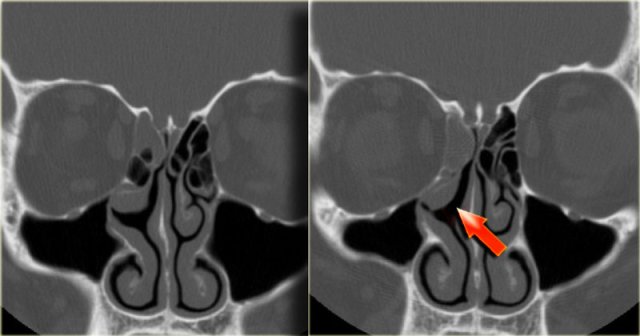

Keratocyst Keratocyst

The corresponding CT shows elevation of the maxillary bone (blue arrow).

The red arrow in the right image indicates the cyst dissecting around the root of a tooth.

This is also a keratocyst.